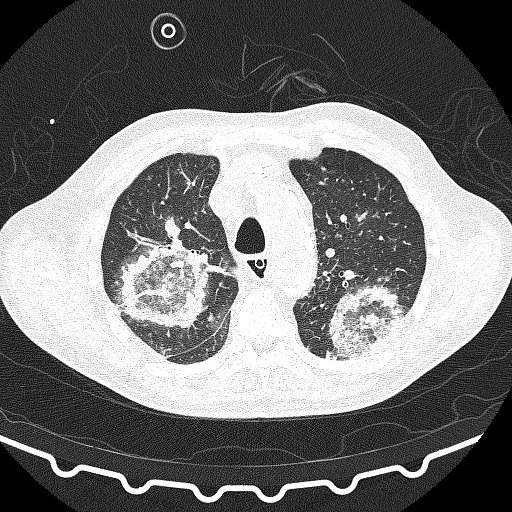

Atoll Sign (Reverse Halo Sign)

• Atoll = circular island with water in the middle (looks like a doughnut)

• Central ground glass opacity with consolidative/enhancing rim

• DDx:

• Cryptogenic organizing pneumonia - main cause

• Fungal pneumonia

• Wegeners (granulomatosis with polyangitis)

• Sarcoid or TB

• Others